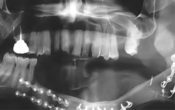

La prise en charge implanto-prothétique d’un patient édenté complet est une situation fréquente mais qui peut sembler difficile en début d’exercice. Jérémie Perrin nous parle des prothèses amovibles implanto retenues à travers les écueils à éviter (mode d’assemblage, empreinte, maintenance).